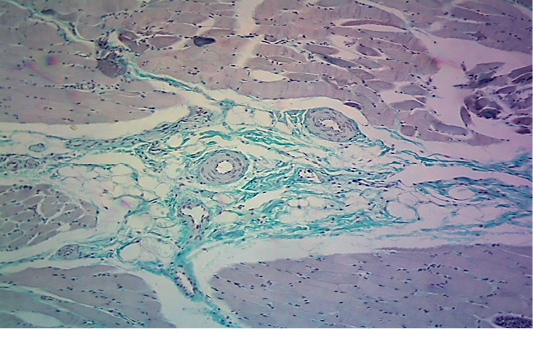

Microscopic image of calf’s heart (“tiger-heart”) from a calf that died from an acute form of FMD, showing interstitial deposition of collagen fibers in green color, with infiltration of mononuclear inflammatory cells in perivascular position (arrow) between collagen fibers. (Masson trichrome stain, 200x.).